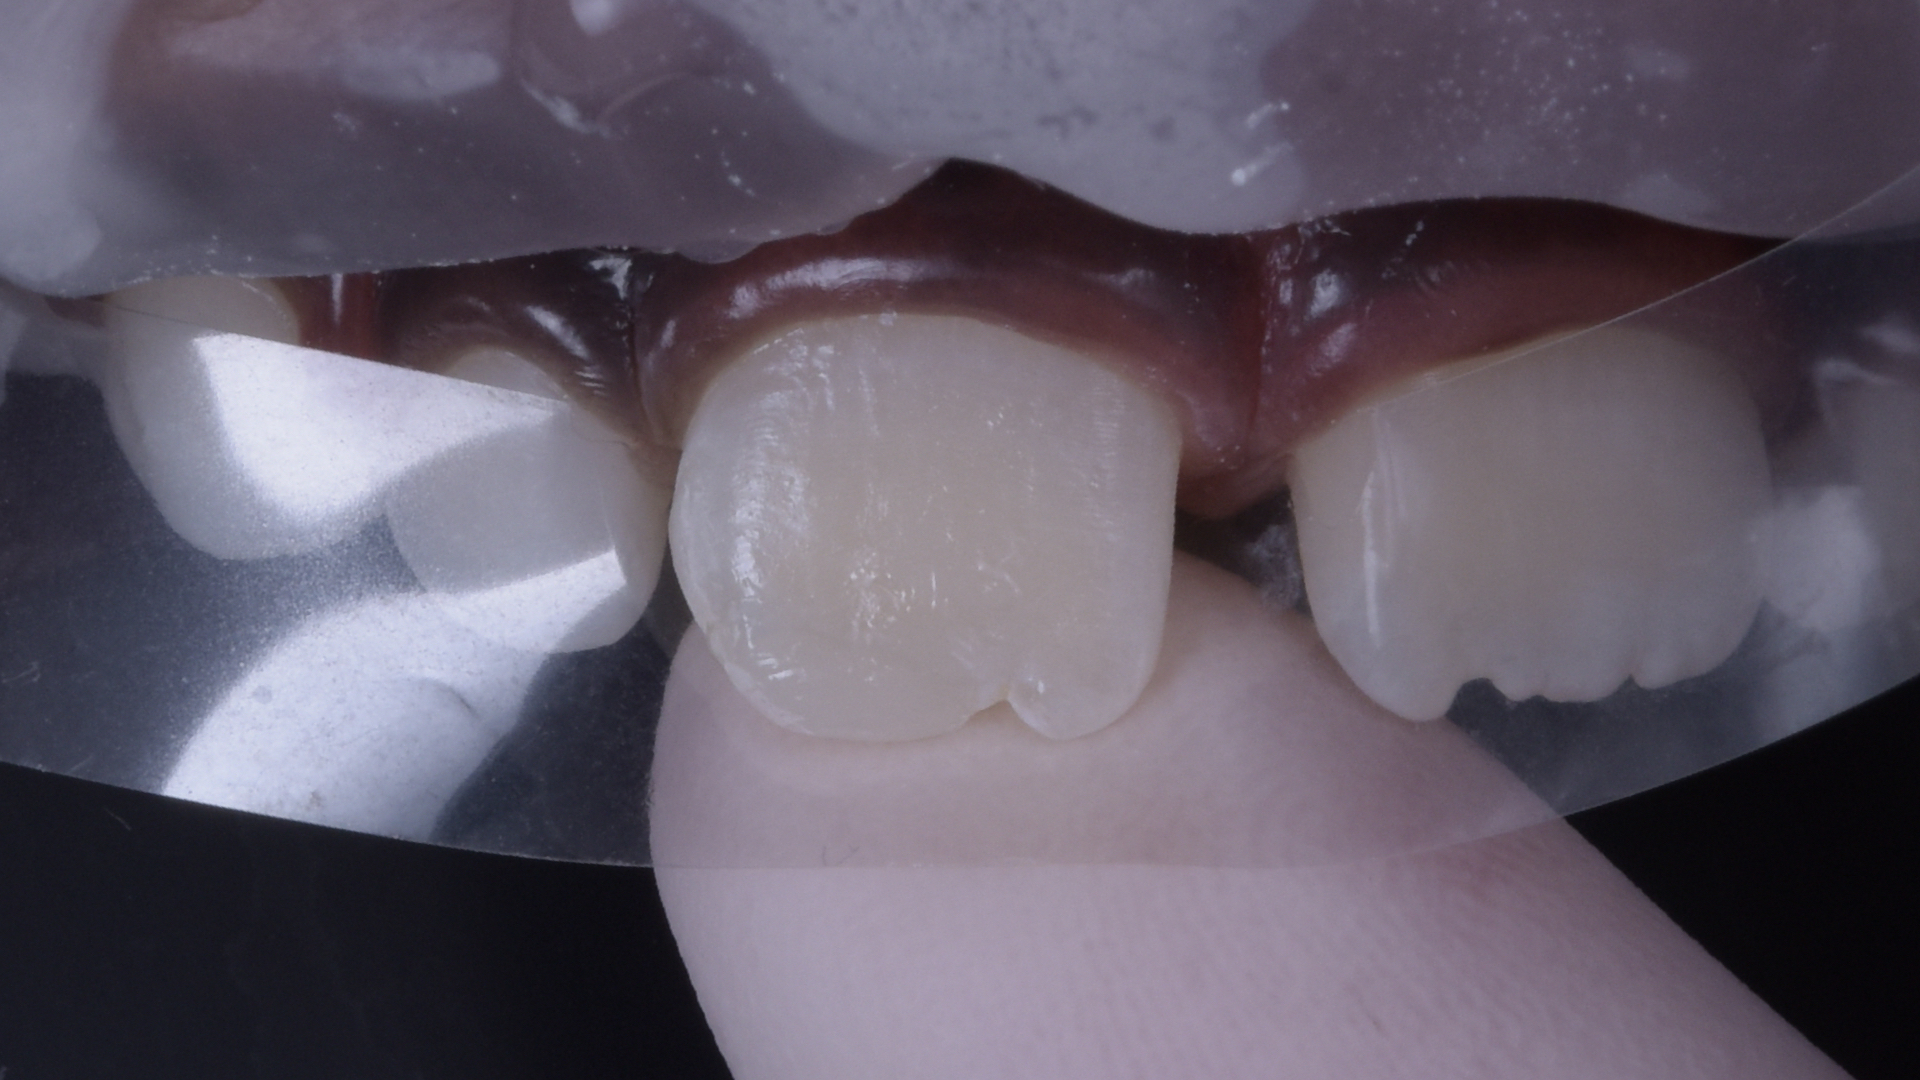

Detailansicht des frakturierten Zahnes.

Ansicht von lateral.